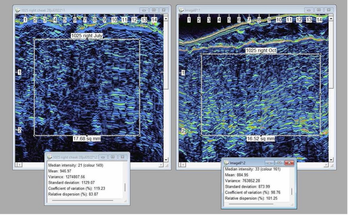

The study conducted by Wayne Carey, MD, Professor of Dermatology at McGill University in Canada evaluated 21 subjects utilizing this formulation for 3 months, using pre and post ultra-high resolution ultrasound imaging of the facial skin. There was an average of 28% increase in subdermal echogenic density (which correlates with collagen/elastin elements). The top quartile of participants demonstrated an average of 51% improvement in collagen over 3 months, the study showed.

PHOTO CAPTION: HIGH-RESOLUTION DERMAL ULTRASOUND SCAN OF ONE OF THE CLINICAL TRIAL VOLUNTEERS COMPARING THE INITIAL SKIN TO 3 MONTHS OF THE GHK-CU GEL USE. THE BRIGHTER THE IMAGE, THE HIGHER THE COLLAGEN DENSITY.